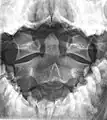

Second cervical vertebra, or epistropheus, from above

In anatomy, the axis (from Latin axis, "axle") is the second cervical vertebra (C2) of the spine, immediately inferior to the atlas, upon which the head rests.

The axis' defining feature is its strong odontoid process (bony protrusion) known as the dens, which rises from the superior aspect of the bone.